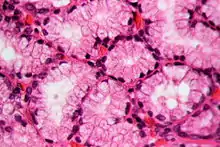

In staining during microscopic examination for diagnosis or research, acid dyes are used to color basic tissue proteins. In contrast, basic dyes are used to stain cell nuclei and some other acidic components of tissues.[8] Regarding cellular structures, acid dyes will stain acidophilic structures that have a net positive charge due to the fact that they have a negatively charged chromophore. Acidophilic structures include the cytoplasm, collagen and mitochondria. The two have an affinity for each other due to the conflicting charges.[9][10] Examples of acid dyes used in medicine include:[11]

- Lee's stain (stains reddish-pink).

- Phosphotungstic Acid Hematoxylin (PTAH) stain (stains blue).

- Eosin stain (stains pinkish-orange).